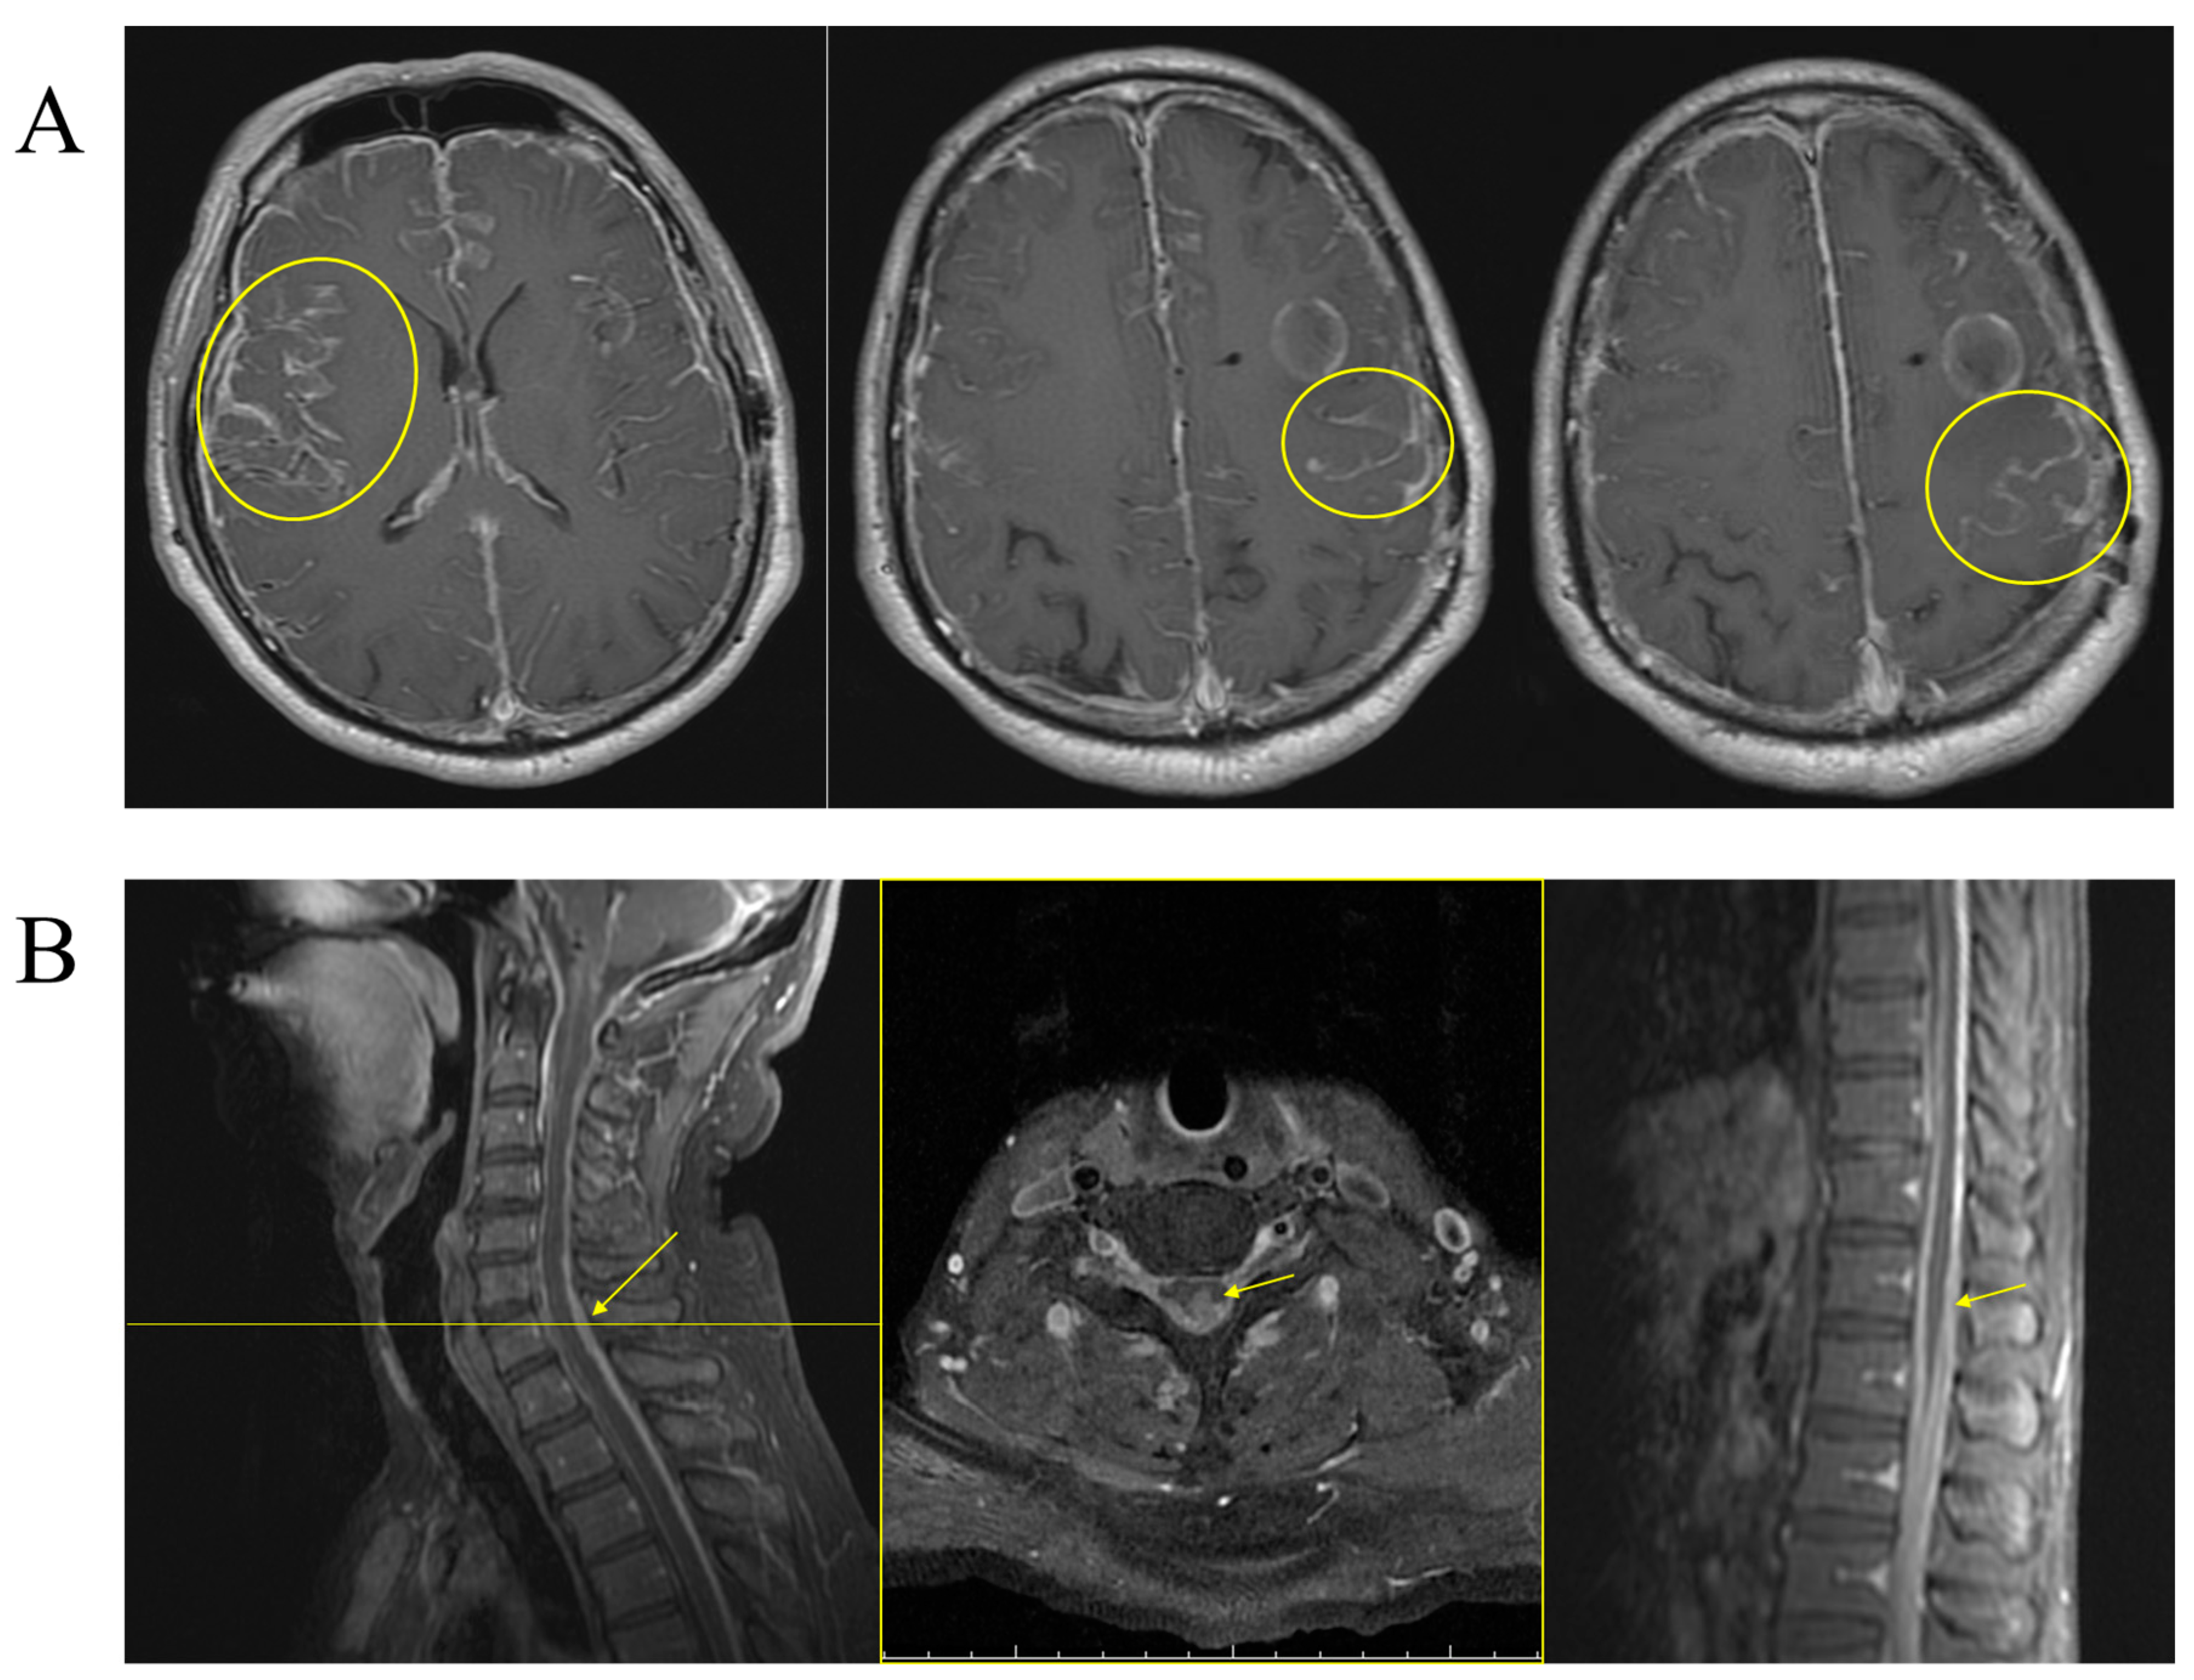

2. Case Presentation